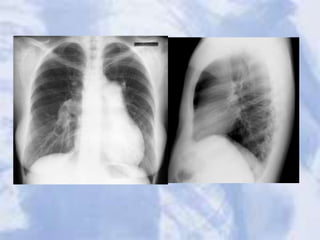

LUL Atelectasis: Loss of heart borders/silhouetting. Notice

over inflation on unaffected lung